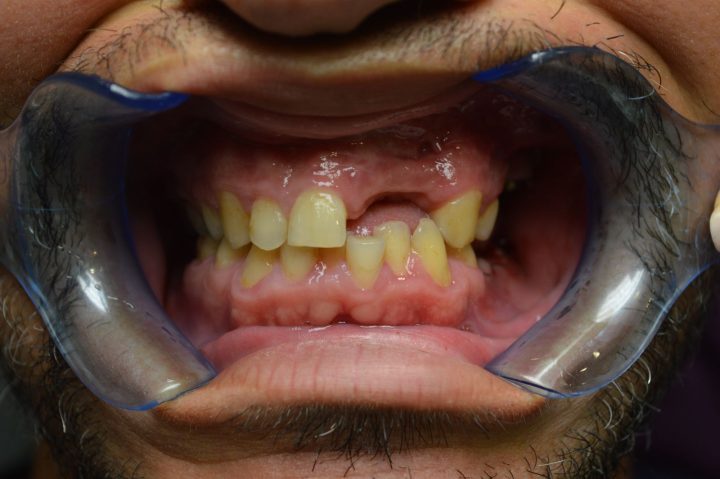

Chris

Chris ist ein 31-jähriger Engländer. Wegen dem unsystematischen Lebensstil und der nachlässigen Zahnreinigungsgewohnheit sind ein paar Zähne bis seinem 30. Geburtstag übrig, und sind in rettungslosem Zustand.

Als er die Klinik besucht hat, konnte nicht mehr essen, weil er immer unter Kieferschmerzen gelitten hat. Aufgrund von der CT-Aufnahme hat Frau. Dr. Erdélyi den Behandlungsplan erstellt. Die übrigen Zähne wurden aus dem Grund von einer großen Entzündung entfernen.

In der gleichen Behandlung hat er noch oben 4, und unten 6 Implantate bekommen, daneben hat er im Ablauf den 5 Tagen provisorischen Zahnersatz gekriegt.